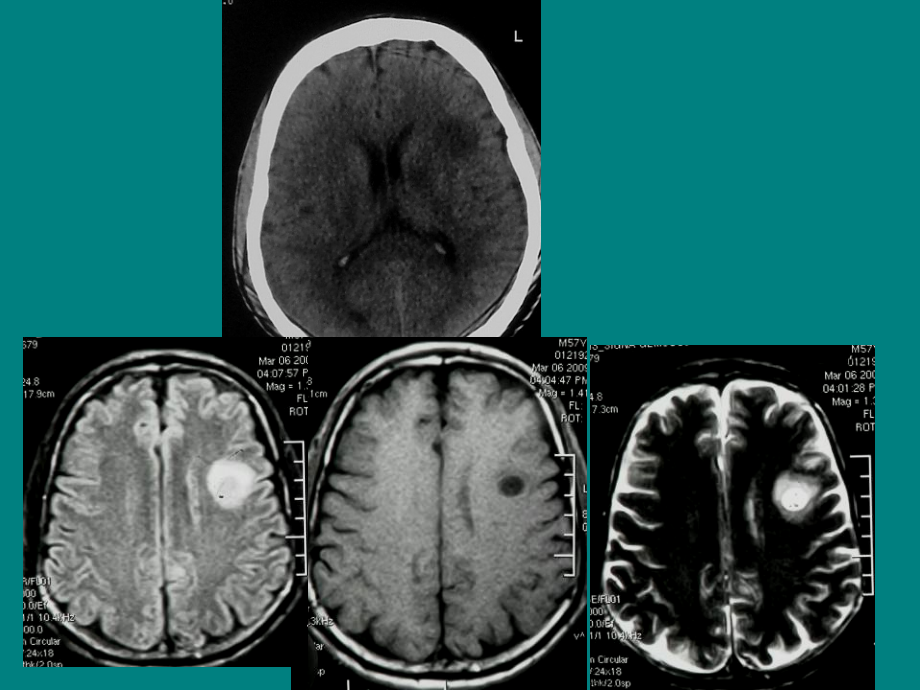

单击此处编辑母版标题样式,单击此处编辑母版文本样式,第二级,第三级,第四级,第五级,*,*,肿瘤样脱髓鞘病变,(,Tumefactive demyelinating lesions,,,TDLs,),影像特征以及鉴别诊断,MRI,增强,中枢神经系统原发性炎性脱髓鞘病,特点:以神经纤维脱髓鞘及小血管周围炎性细胞浸润为主要病理表现的一组疾病,典型表现为白质内多发、弥散的异常信号,病灶通常无明显占位效应,包括,多发性硬化,视神经脊髓炎,急性播散性脑脊髓炎等,肿瘤样脱髓鞘性病变,(,Tumefactive demyelinating lesions,,,TDLs,),但一些非典型病例,表现为占位性肿块的脱髓鞘性病变,从临床、影像学甚至病理学冰冻切片都很难与中枢神经系统肿瘤如胶质瘤、淋巴瘤等鉴别,Tumefactive demyelinating lesions,1979,年,,Van Dor Velden,首次对该病进行了报告。,关于这种临床综合症是否属于一种独立的疾病仍然存在争论,,目前归类为多发性硬化和急性播散性脑脊髓炎之间的独立中间型,。,肿瘤样炎性脱髓鞘性病变,(tumor-like inflammatory demyelinating diseases,TIDD,),肿瘤样脱髓鞘病变,(tumor-like masses of demyelination),脱髓鞘假瘤,(demyelinating pseudotumor lesion),、,假瘤样脱髓鞘病,(,pseudotumor formus of demyelinating disease,临床表现,该病多为单时相,对激素治疗敏感,平均年龄,33-36,岁,可急性、亚急性或慢性起病,以急性起病多见,随病程延长,病情逐渐趋于稳定,与多发性硬化不同,其病情无缓解及复发交替的特点;,不发生于感染或接种疫苗后,实验室检查,常规及脑脊液检查大多正常。少数低热患者可有白细胞升高和脑脊液蛋白含量升高;脑脊液白细胞可升高,病理表现,急性期或亚急性期的主要病理改变,神经髓鞘的破坏,而神经轴索保留完好。,光镜下可见大量淋巴细胞在血管周围呈袖套状浸润,而髓鞘破坏区则以大量单核细胞和泡沫状巨噬细胞浸润为主、同时伴有较多的肥胖型星形细胞增生。病变区内还可见出血或坏死。,随着病程延长,巨噬细胞和肥胖型星形细胞逐渐减少,纤维型星形细胞明显增生,病变开始趋于稳定,,此时无论病理或影像学均易误诊为纤维型星形细胞瘤,。,影像表现,一般为,CNS,白质内孤立病灶(大于,2cm,),少数多发;,Kepes,统计孤立病灶占,77,4,(24,31),,多发病例占,22,6,(7,31),病灶分布以脑室旁白质为主,单发肿块样病变,圆形或不规则形,灶周水肿程度轻至中度,肿块体积与占位效应不成比例,CT,表现,急性或亚急性起病者多表现为低密度,少数呈等密度或高密度,密度均匀或不均;伴急性出血时低密度灶内可见片样高密度区;伴坏死、囊变时可见局灶性更低密度区;如病变区尚保留有正常脑组织或新旧病灶重叠,则可表现为低、等混杂密度。,慢性起病者可表现为低、等或高密度,水肿程度及占位效应比急性起病者更不明显。,增强扫描病变多呈弥漫性强化或环形强化,少数不强化,MRI,表现,多表现为均匀长,T1,、长,T2,信号,合并出血时呈短,T1,、长,T1,混杂信号,有囊变时呈不均匀长,T1,、长,T2,信号。,急性起病者增强扫描多表现为弥漫性强化;随着病灶中心坏死和周围出现新病灶,则表现为环形强化,非闭合性环行强化,(openring sign,),(77%),,口朝向皮质,灰质侧不强化。,强化环代表脱髓鞘的前缘,因此通常面对白质。,NEUROLOGY,2007,A previously healthy 31-year-old woman presented with a 2-week history of progressive left hemiparesis.,21-year-old woman presenting with new-onset seizure and biopsy-proven tumefactive demyelinating lesion.,垂直脱髓鞘征,(Dowsons fingers,)有垂直于侧脑室表面的倾向;在矢状位、冠状位脑室旁病灶可以观察到,病灶可以呈条索状、火焰状,长轴垂直于侧脑室,也有闭合性增强,Multiple Sclerosis Dawsons,Fingers,Mechi,等 认为具有强化效应的病灶是新的活动性病灶,而,环形强化则提示病灶病程小于,1,个月,。同时有强化和非强化两种病灶时,表示病灶处于不同时期,或者脱髓鞘病灶在不断的发生,新鲜病灶,在,DWI,上呈轻中度高信号,但低于急性脑梗死病灶,一般高于肿瘤,T2,序列或,SW,影像上病变中心可见,扩张血管样结构走行,,意味着向扩张室管膜下静脉引流,MRS,可能对于诊断有帮助,,MRS,显示谷氨酸盐和谷氨酰胺峰,这在高等级的胶质瘤是看不到,小静脉,肿瘤样波谱,胼胝体累及,提示,TDLs,影像征象,相对特异性的征象,肿块体积与占位效应不成比例,非闭合性环状强化,病灶中心扩张小静脉,激素治疗有效,非特异性征象,胼胝体侵犯,弥散增强,类肿瘤样,MRS,激素治疗后好转,50-year-old man presenting with slurred speech and biopsy-proven tumefactive demyelinating lesion,2 months after corticosteroid therapy,鉴别诊断,单发多见,往往,80,以上误诊为胶质瘤而行手术,胶质瘤,淋巴瘤,脓肿,多发性肿瘤样脱髓鞘病,多发性硬化、,急性播散性脑脊髓炎,Balo,病同心圆硬化,转移瘤,淋巴瘤鉴别,与肿瘤鉴别,-,胶质瘤 淋巴瘤,临床表现比肿瘤明显,MRI,强化的区域,CT,上呈低密度,是区别淋巴瘤或胶质瘤鉴别诊断特征之一;胶质瘤等或低密度,淋巴瘤一般等或高密度;,DWI,均匀略高信号,,CT,等高密度,基本可以排除,TDLs,,,TDLs,非闭合性增强是鉴别诊断的依据之一;,非脱鞘病,(,炎症、肿瘤等,),只有,7%,出现非闭合性环形增强,TDLs,水肿程度及占位效应相对较轻,Distinguishing Tumefactive Demyelinating Lesions from Glioma or Central Nervous System Lymphoma:Added Value of Unenhanced CT Compared with Conventional Contrast-enhanced MR Imaging,Radiology 2009,251,(,2,):,467-484,TDLs,MR imaging and CT findings in 30-year-old woman with TDL.A,Axial T2-weighted and,B,con-trast-enhanced axial T1-weighted MR images show a round mass with complete rim enhancement and perilesional edema in left frontal white matter.The signal intensity of the rim is isointense to gray matter on the T2-weighted image(arrow).C,Unenhanced axial CT image shows hypoattenuation(grade 1)of the rim;the margin of the enhanced rim on the MR image is not discernible on unenhanced CT image.,胶母,MR imaging and CT findings in 54-year-old woman with glioblastoma,.,A,Axial T2-weighted and,B,contrast-enhanced axial T1-weighted MR images show a round cystic mass with complete rim enhancement and peritumoral edema in the subcortical white matter of the right frontal lobe.The signal intensity of the rim is isointense to gray matter on the T2-weighted image(arrow).C,Unenhanced axial CT image demonstrates isoattenuation(grade 2)of the rim(arrowhead).,TDLs,胶母,Glioblastoma Multiforme:no dark line of advancing demyelination,胶母,TDL,MR imaging and CT findings in 32-year-old man with TDL.,A,Axial T2-weighted and,B,contrast-enhanced axial T1-weighted MR images demonstrate white matter lesions with heterogeneous enhancement in the parietal lobe and corpus callosum.The signal intensity of the enhancing components of the right parietal lobe is mixed(isointense plus hyperintense)on the T2-weighted image.C,Unenhanced axial CT image shows hypoattenuation(grade 1)of both the enhanced and unenhanced components of the lesions(arrows).,与淋巴瘤鉴别,MR imaging and CT findings in 65-year-old woman with lymphoma,.,A,Axial T2-weighted and,B,contrast-enhanced axial T1-weighted MR images demonstrate bilateral lesions with diffuse enhancement in the white matter of both parieto-occipital lobes.Signal intensities of the enhancing lesions are hyperintense on the T2-weighted image.C,Unenhanced axial CT image demonstrates isoattenuation(grade 2)of the lesion in the left parietal lobe(arrowhead).,淋巴瘤,T1WI C+,肿瘤位于侧脑室旁,形状和轮廓均不规则,明显增强。,(例),脓肿,女性,,47,岁,出现持续数个月的虚弱,The mass has well defined borders and partially effaces the atrium(trigone)of the left lateral ventricle.There is mild patchy enhancement.DWI images demonstrate increased signal throughout,but only the even more hyperintense rim demonstrates true restricted diffusion on ADC images.The remainder of the mass is increased signal on ADC images,indicating increased diffusivitiy.,脓肿,多发性硬化,多发病灶与,MS,难鉴别,占位效应明显,肿瘤样脱髓鞘病变长期随访复发少见(,Kepes,等随访,31,例,9-12,年,,28,例未复发),F 28Y,,病灶呈类圆形,病灶位于两侧脑室旁、右侧颞叶及胼胝体。,MS,多发病灶,“,黑洞”、“核心”,+“,晕环”现象,转移瘤,皮髓交界处多见,水肿广泛,而肿瘤样脱髓鞘病变分布在深部脑白质,年龄,1,,病灶多发,2,,两侧脑室旁及额顶叶深部白质,3,,病灶较大,部分病灶呈融合状,4,,信号:与急性,MS,病灶相似,5,,强化:结节状,急性或亚急性起病,多见于儿童及青少年。病前多有病毒感染或疫苗接种史,病变以静脉性脱髓鞘主 累及范围广泛常同时累及脑和脊髓病程急,急性播散性脑脊髓炎,播散性脑脊髓炎,Balos concentric sclerosis,(,BCS,)同心圆硬化,一种少见的脱髓鞘病变,被认为是多发性硬化的一种变异,病理学上表现为环状正常髓磷脂或髓鞘再生与脱髓鞘病变相交替,累及大脑半球、脑干、脊髓和视交叉。,病变位于脑室周,类似于其他的多发性硬化,常多发以顶叶半卵圆中心多见,层状(洋葱皮样、“年轮状”,-,提供诊断线索,是所谓的“,Aunt Minnie,”,以下临床特点时应考虑脱髓鞘假瘤,年轻病人急性或亚急性起病;,影像学检查显示脑内有孤立的、以白质为主的病灶,其水肿及占位效应较轻;病灶的强化呈非闭合性或垂直于脑室;,试行激素治疗后病灶水肿或强化明显减轻以至消失。,M,10,岁,病理血肿?,谢谢!,